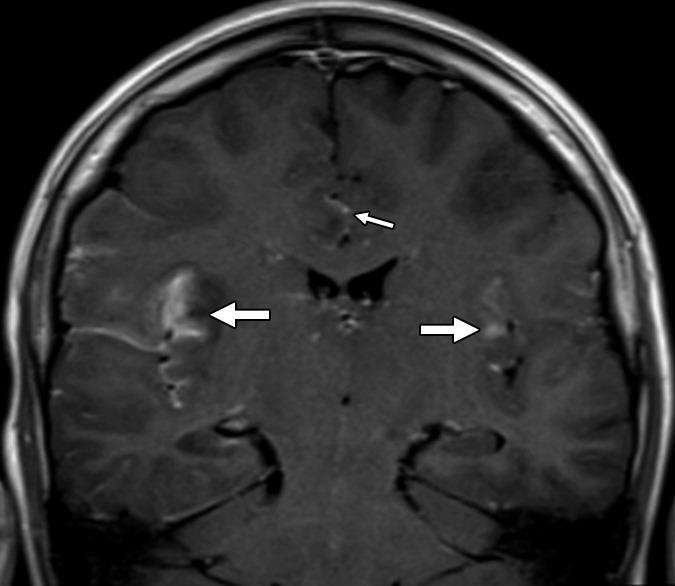

Т1-взвешенное корональное изображение после введения контраста демонстрирует асимметричное двустороннее гириформное и лептоменингальное контрастное усиление больше в области коры островка (большие стрелки) и поясной извилины (меньшая стрелка)

о Изменение сигнальных характеристик коры медиальных отделов височных и нижних отделов лобных долей в сочетании с ограничением диффузии на ДВИ

о Высокая вероятность вовлечения поясной извилины и контрлатеральной височной доли

о Лимбическая система: обычно височные, островковые доли, обсубфронтальная область, поясные извилины

о Обычно двустороннее, но асимметричное поражение

о Обычно наблюдается «щажение» базальных ганглиев